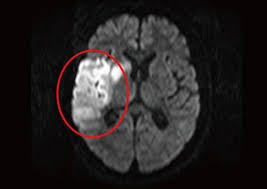

まず、MRIが得意とするのが脳と神経の検査です。例えば、脳梗塞の早期発見や眩暈・しびれの原因検索などに使用されます。CTでは分かりにくい脳の細かな変化もMRIでは映し出すことができます。

脳・神経(脳梗塞など)